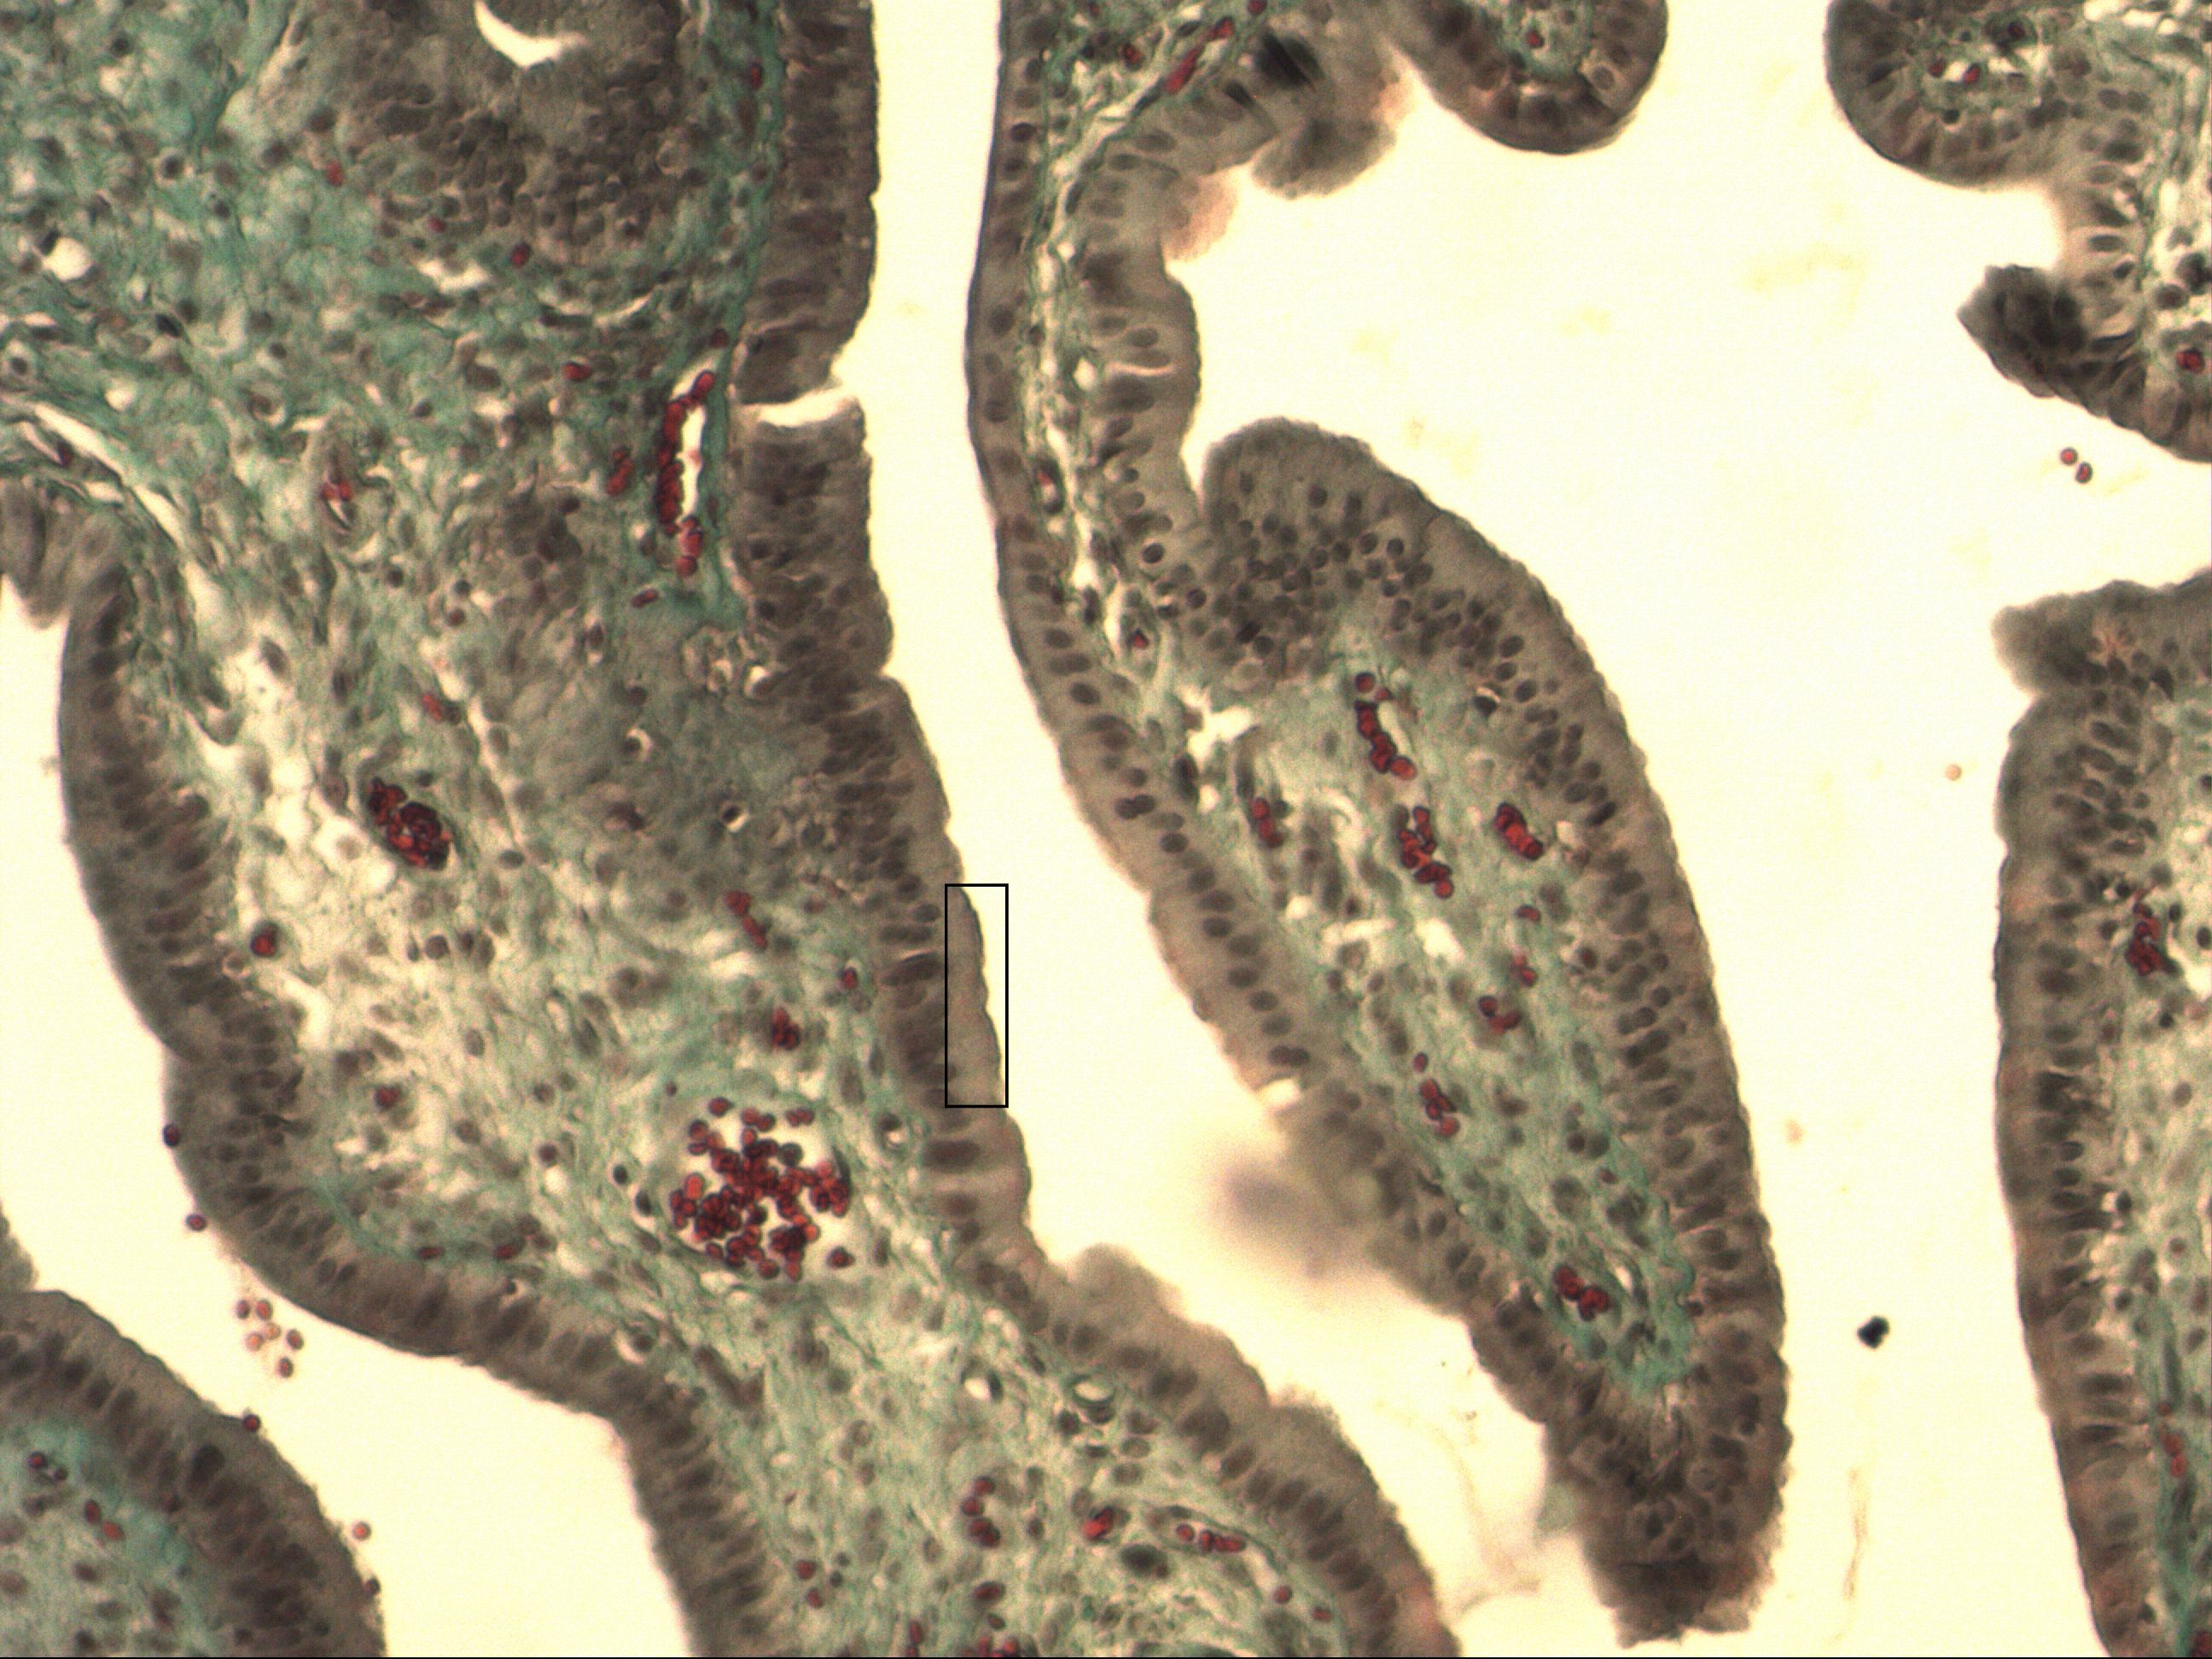

Einschichtiges hochprismatisches Epithel

Gallenblase [Trichrom]

Der Schnitt aus der Gallenblase zeigt ein einschichtiges hochprismatisches Epithel mit Mikrovilli zur Resorption.